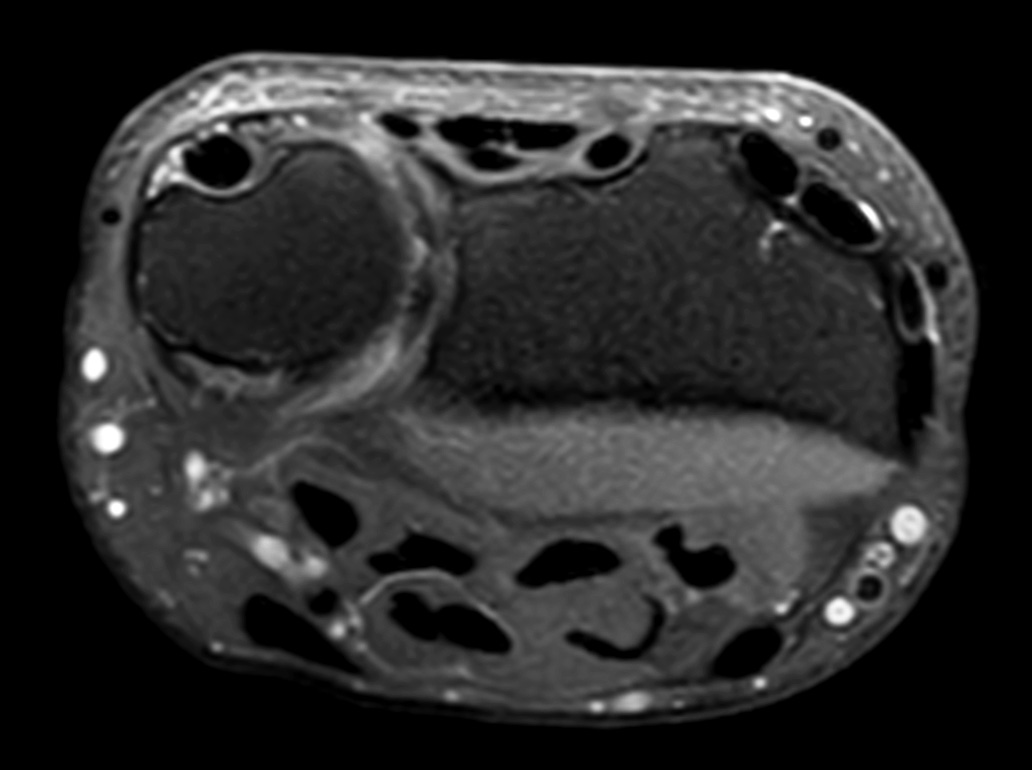

Comprehensive wrist imaging